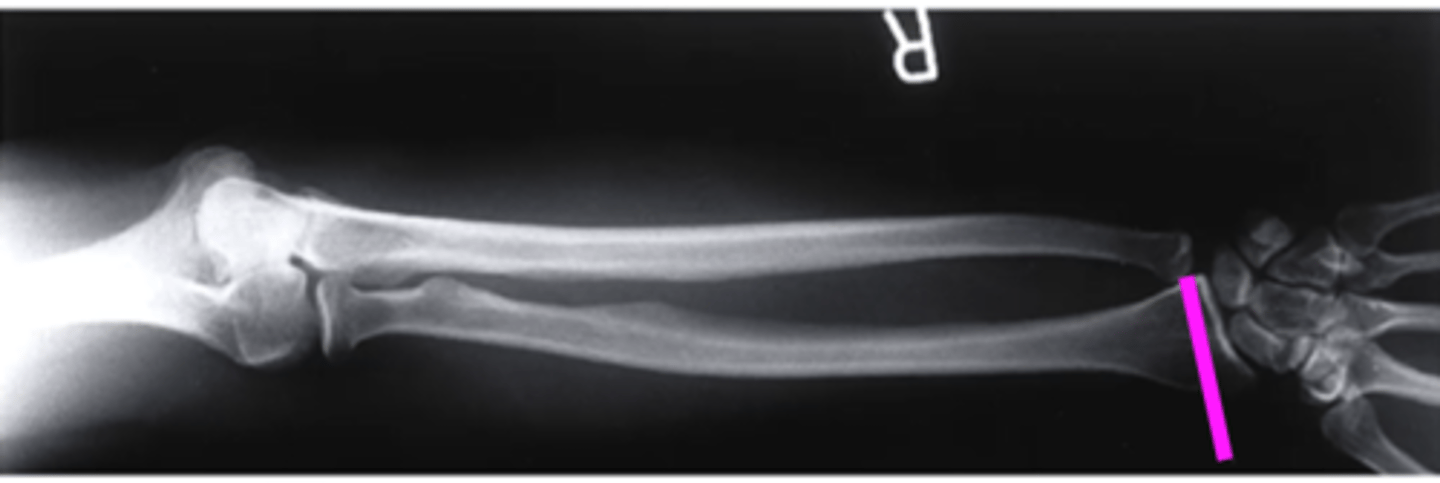

lateral forearm

what view is this

olecranon process

what does this pink line point to?

ulna

radius

radiocarpal joint